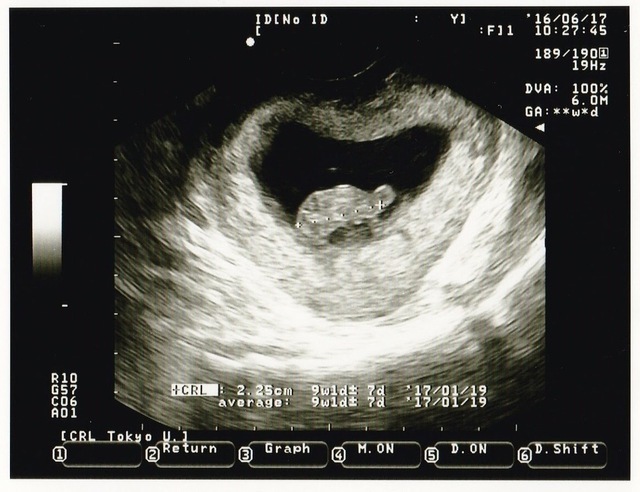

9週1日(9w1d・女の子)|きういゆず さん(26歳)

エコー写真撮影時のエピソード:

初めて旦那さんと検診に行った日のエコーです。

ハートの中に亀さんがいるようなエコーで旦那さんと笑いあったことを思い出します。 まだまだ人間らしい形をしていないのに、こんなに愛おしく感じれるのかと感動しました。